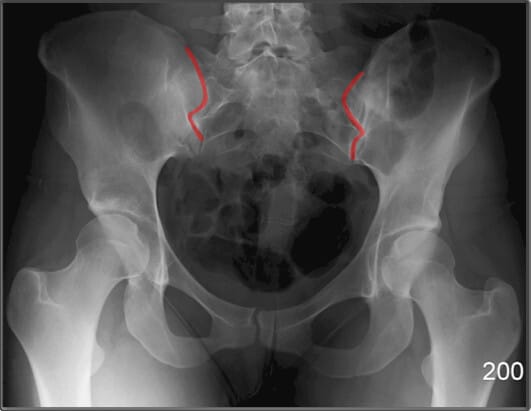

천장관절 (Sacroiliac Joint)

| 천장관절 (Sacroiliac Joint) |

| ✅ 천골과 장골 사이의 관절로, AP view상에서 좌우 대칭적으로 좁고 긴 틈으로 관찰됩니다. |

| 🔴 간격이 좁아지거나 불규칙한 경우 염증성 질환(예: 강직성 척추염)을 의심할 수 있습니다. |